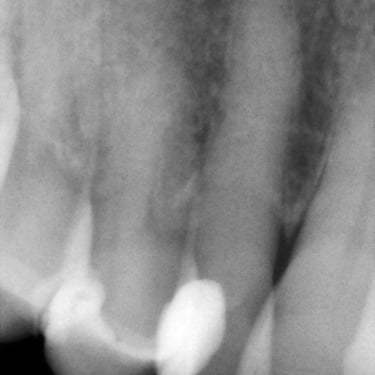

Caries Radicular

La caries radicular es la descomposición del cemento y la dentina en la raíz del diente, común en personas mayores con recesión gingival.

Los pacientes pueden experimentar sensibilidad y dolor en la raíz expuesta.

El tratamiento incluye la eliminación de la caries y la restauración de la raíz. La prevención incluye una buena higiene oral y el uso de flúor.